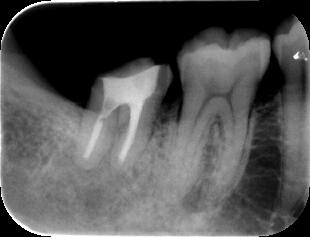

(1)不十分な根管(神経の通っていた管)治療が原因で右下の顎が腫れています。(↑病巣

当初は抜歯を考慮しました(上左図)が、根の治療を丁寧に行うことによって、半年後には

ほぼ問題の無い程度(上右図)にまで骨が修復され十分に機能が回復されました。